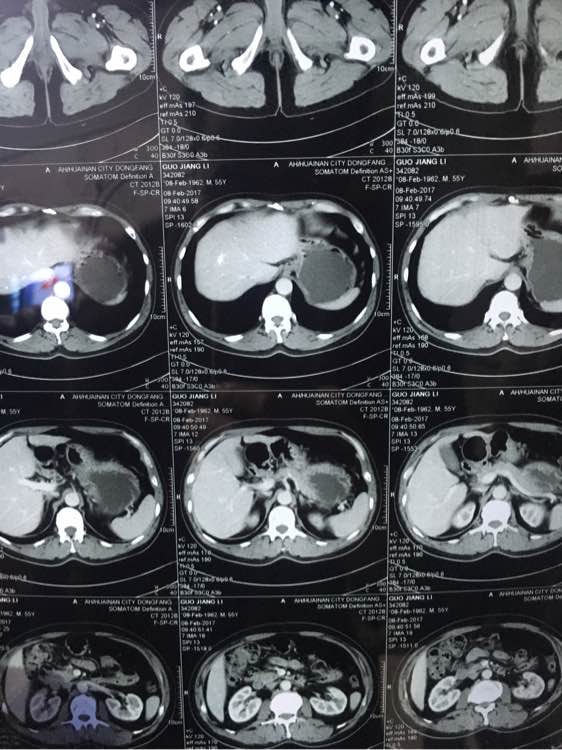

大神看下,几个月前说肠子

ct吧

几个月前说有点东西,肠子上

兄弟 你拍的有点多啊 全腹部ct?